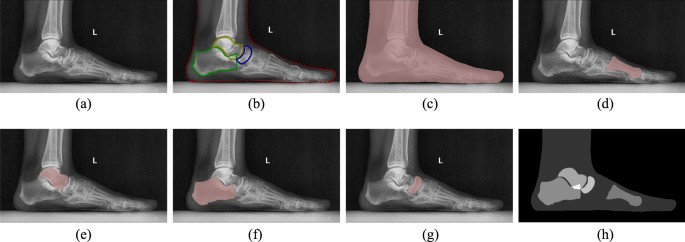

Additionally, to enhance the robustness and generalization capability of the model, we employed the Contrast Limited Adaptive Histogram Equalization (CLAHE) algorithm for contrast enhancement34, and converted the 16-bit X-ray image into 8-bit images with sufficient contrast. Subsequently, image normalization is performed to reduce differences in brightness and contrast, mitigating the model’s susceptibility to outliers or extreme pixel values. Next, in order to reduce computational complexity and memory usage, we utilized the bilinear interpolation method35 for resizing the original images to a unified size of 384 × 576 pixels as input for the model, and ensured that the key semantic information in the images was preserved. Figure 2 illustrates an example weight-bearing lateral foot X-ray image.

A weight-bearing lateral foot X-ray image and manually annotated ground truth: (a) the original grayscale image parsed from the DICOM file serves as the input to the model; (b) the manual labeling results using the Labelme library, stored as a JSON file; (c)–(g) the boundaries of the entire foot, FM, TA, CA and NAVI bones obtained from parsing the JSON file. Here, for visual clarity, these label boundaries are overlaid on the original image for visualization, though each labeled image is actually a binary black-and-white image; (h) visualization of various labeled images with different pixel values overlaid on one image.